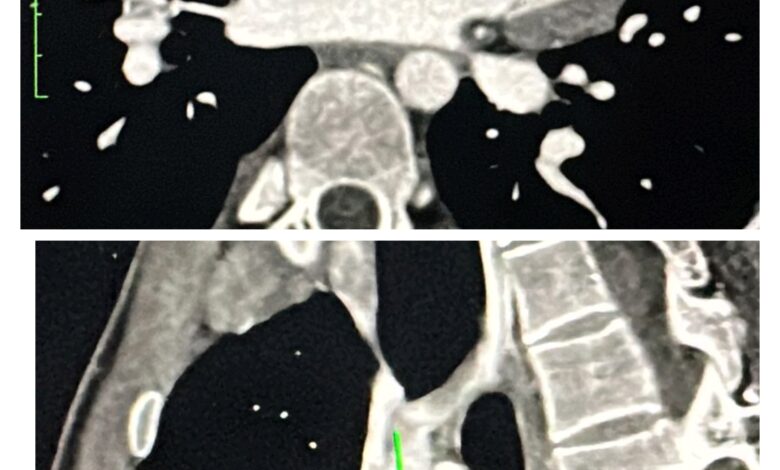

एम्स भोपाल ने पहली बार साइनस वेनोसस एट्रियल सेप्टल डिफेक्ट (ASD) का क्लोजर एक हाइब्रिड कवर स्टेंट की मदद से सफलतापूर्वक किया। यह उपलब्धि हृदय रोग उपचार के क्षेत्र में एक अहम कदम है। यह उन्नत प्रक्रिया विश्व-भर में तेजी से स्वीकार की जा रही है, हालांकि उत्तर भारत के केवल कुछ ही केंद्र इस तकनीक का उपयोग कर रहे हैं। इस जटिल मामले में रोगी की संरचना चुनौतीपूर्ण थी। इसमें एक अतिरिक्त दाहिनी ऊपरी पल्मोनरी वेन (RUPV) मौजूद थी, जिसे प्रक्रिया के दौरान बंद होने से बचाना आवश्यक था। इसके अलावा, सीवीसी-आरए (SVC–RA) जंक्शन काफी चौड़ा था, जिसके लिए स्टेंट का विशेष तरीके से फैलाव करना जरूरी था ताकि रक्त प्रवाह सुचारु बना रहे। टीम ने एक विशेष हाइब्रिड कवर स्टेंट का उपयोग किया, जिसके एक सिरे पर 15 मिमी का अनकवर्ड भाग होता है। अतिरिक्त नस की सुरक्षा के लिए, 5F JR कैथेटर को कवर और अनकवर भाग के जंक्शन पर स्टेंट स्ट्रट्स के बीच से सावधानीपूर्वक निकाला गया। इसके बाद, 28 मिमी BMV बैलून का उपयोग करके स्टेंट को सही तरीके से फिट किया गया और किसी भी शेष शंट को समाप्त कर दिया गया।

यह तकनीक, जिसमें RA–SVC जंक्शन पर बैलून से फ्लेयरिंग की जाती है, अब तक वर्णित नहीं की गई थी। परिणाम पूरी तरह सफल रहा। RUPV का पूरा रक्त प्रवाह बिना किसी रुकावट के बाएँ आलिंद (Left Atrium) में पहुंचाया गया। यह उपलब्धि एम्स भोपाल के लिए एक नया मील का पत्थर है और यह दर्शाती है कि संस्थान दुर्लभ और जटिल हृदय उपचारों में भी उत्कृष्टता की ओर अग्रसर है।